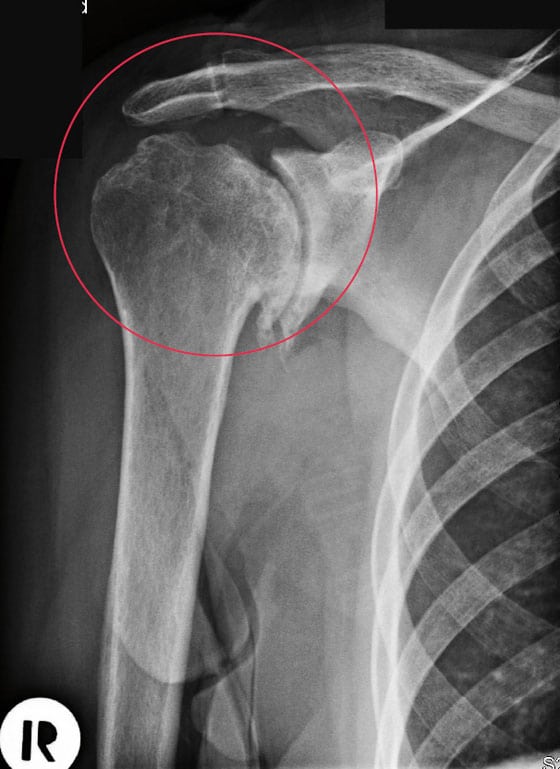

Появление специфического хруста в плечевом в суставе означает изменение хрящевой и костной ткани, ограничивающие движение руки. Постоянная и сильная боль, спазмы мышечной ткани и ощущение жжения в соседних суставах. При рентгенографическом обследовании на снимках будет видно изменение суставных поверхностей хряща, сужение полости, сращение синовиальных оболочек между собой и другие изменения.